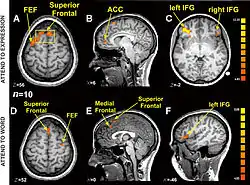

Research using functional magnetic resonance imaging of the brain suggests that cognitive and affective-expressive forms of communication and self-reflection have distinct neural bases.[50] Clinical findings have long suggested that verbalizations are often very incoherent when the individual is trying to put into words something deeply emotional.[51] Identification of words naming emotions (happy, neutral, sad) was found to be faster than identification of corresponding facial expressions. Recognition of face expressions was more difficult to suppress in favor of the recognition of words than vice versa, the two conditions presenting different patterns of brain activation. These experimental results suggest that reading and recognition of face expressions are stimulus-dependent and perhaps hierarchical behaviors, hence recruiting distinct regions of the medial prefrontal cortex.[48]

- 1 2 Ovaysikia S, Tahir KA, Chan JL, DeSouza JF (January 2011). "Word wins over face: emotional Stroop effect activates the frontal cortical network". Front. Hum. Neurosci. 4: 234. doi:10.3389/fnhum.2010.00234. PMC 3020489. PMID 21258644.